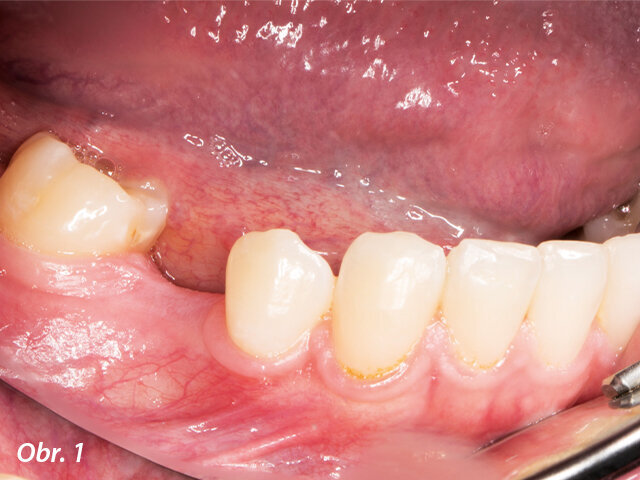

U dvacetileté pacientky byla diagnostikována ageneze stálých druhých premolárů a druhých molárů. O perzistující mléčný druhý molár přišla před několika lety a nyní měla problémy s porušenou okluzí. Pro získání dalších informací o stavu pacientčina chrupu byl pořízen panoramatický snímek pomocí zobrazovacího přístroje Planmeca Promax 2D.

Panoramatický RTG snímek pořízený pomocí rentgenu Planmeca Promax 2D ukázal chybějící stálé zuby.